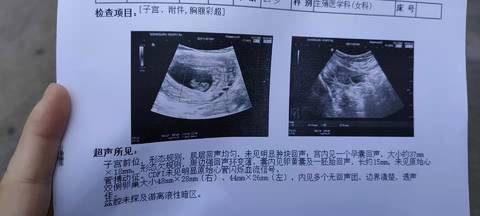

6周检查正常,怎么8周就没胎心了呢?到直接做掉吗?还是要等等呢?

你好,正常情况下怀孕7-8周可以看到胎心,如果月经延后也可以看不到,5天复查彩超,还看不到,可能是胚胎停育。